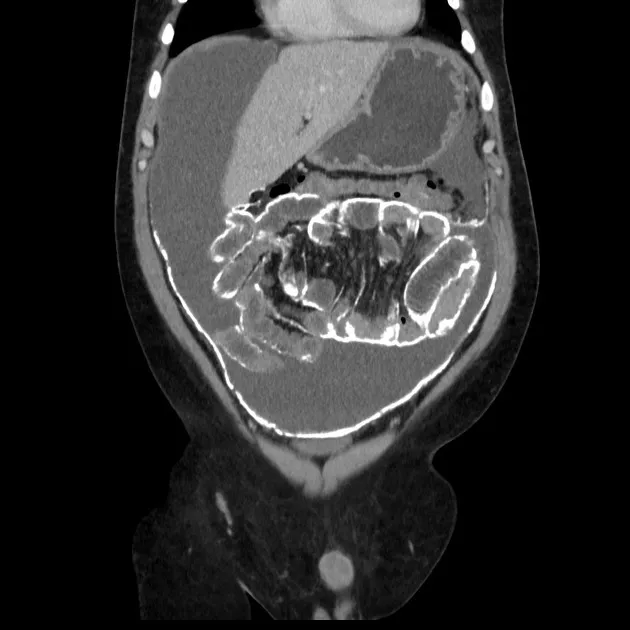

Injúria Renal Aguda (revisão Lancet 2025)